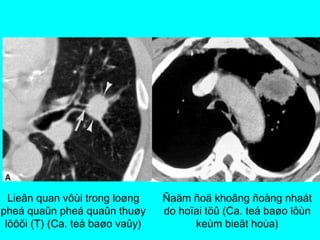

NOÁT PHOÅI AÙC TÍNH

  Bôø khoâng ñeàu, tuûa gai (radiating coronal)

  Co keùo maøng phoåi (Pleural fingers, flaps)

  Hoäi tuï maïch maùu (Rigler’s umbilical sign)

  Hoïai töû

  Ñoùng voâi

  Lieân quan trong loøng pheá quaûn

  Thôøi gian nhaân ñoâi [ 30-400 ngaøy]

Ung thö phoåi ngoïai bieân/ Bôø

khoâng ñeàu, tuûa gai/ Co keùo

Ñaäm ñoä khoâng ñoàng nhaát

do hoïai töû (Ca. teá baøo lôùn

keùm bieät hoùa)

Lieân quan vôùi trong loøng

pheá quaûn pheá quaûn thuøy

löôõi (T) (Ca. teá baøo vaûy)